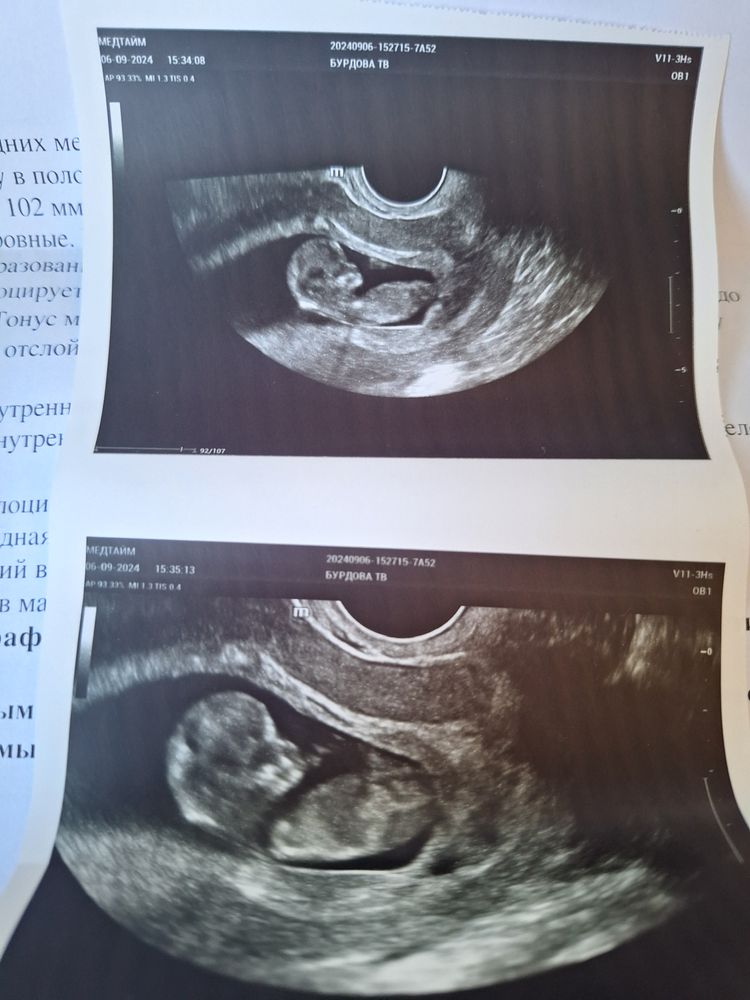

Узи после эко день

Узи после эко день 144 фото